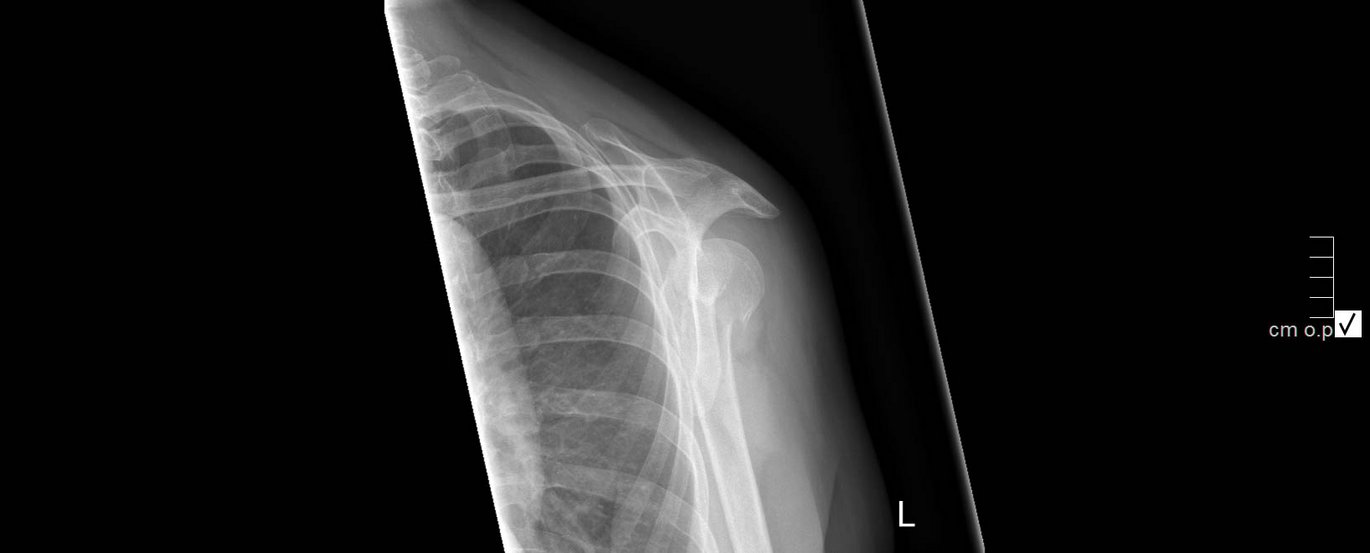

Ny forskning fra AU og AUH viser, at et skulderbrud ikke behøver operation, men at en slynge er lige så god. Foto: Regionshospitalet Viborg

The results are based on a study of 88 patients over the age of sixty, all of whom had fractures of the shoulder of the type where the bones are displaced. This often happens in connection with a fall on the shoulder and the traditional treatment for a displaced shoulder fracture is an operation in which the bones are joined again using plates or metal screws. In the study, half of the patients were operated on, while the other half only had the arm supported by a sling. All 88 patients underwent rehabilitation under the supervision of a physiotherapist and were subsequently followed for two years.

• The patients had what is known as a 2 part displaced shoulder fracture.